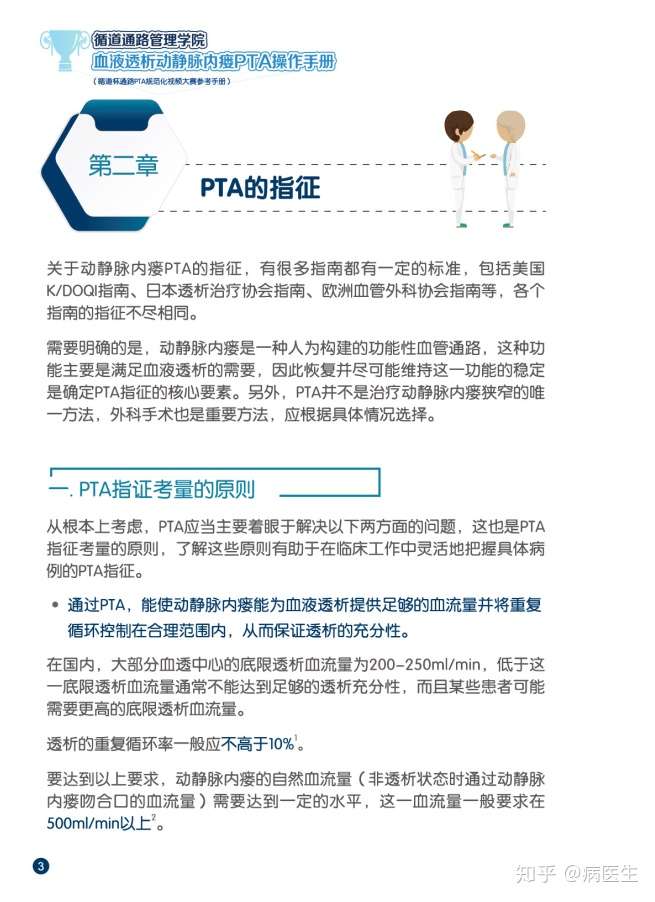

透析pta 診療報酬改定 早わかり1分解説その 透析